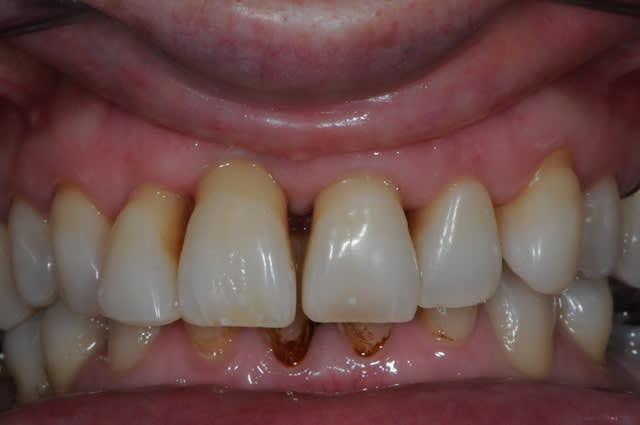

photo 1: j+1 mois et demi

la cigarette à repris de plus bel, je suis désespéré mais bon, avec la chir muco gingival je devrais y arriver.

photo 2: j+3 mois

au mois d'octobre (j+5 mois), et malgré mon insistance, la patiente refusant de mettre en place les greffes muco-conjonctives pour récupérer le fiasco attendu sur 11, on débute la prothèse.

elle ne veut plus continuer, et sa reprise tabagique m'interdit une greffe. c'est vraiment dommage.